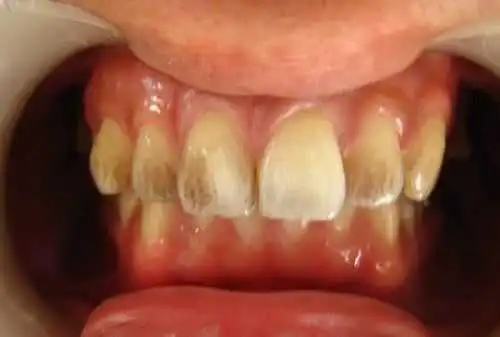

定期洗牙是目前最有效的治疗牙周疾病的方式。下面是洗牙前后的对比图:

洗牙(洁治)后,洁白如一